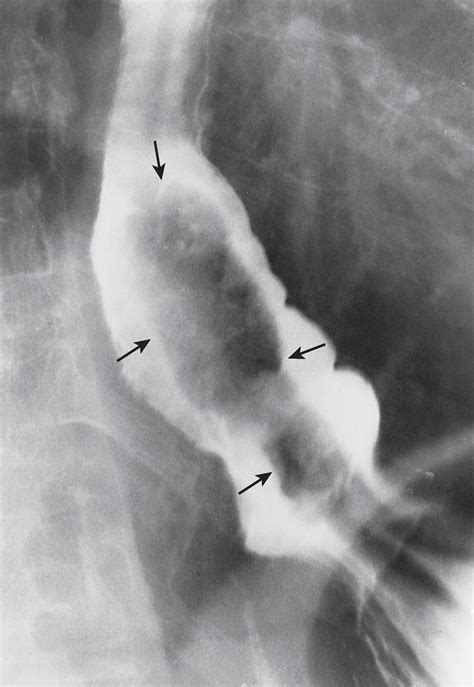

Diagnosing polyps in oesophagus requires a systematic approach. Since these growths rarely cause symptoms until they reach a certain size, doctors rely on imaging and direct visualization. The primary diagnostic tools include:

Barium Swallow X-ray imaging to see how the esophagus functions and if a mass is obstructing flow.